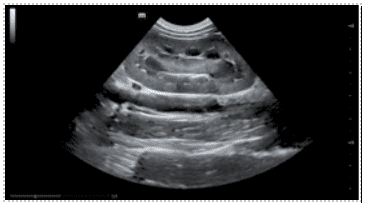

A. In short, yes! Incredibly so, in fact. It is important to note that they have been designed with a specific purpose in mind. Namely, point-of-care ultrasound (POCUS), and the flexibility they offer is, frankly, stunning. Typically, they offer two or more transducer options. Either by virtue of interchangeable ‘heads’, or being ‘double-ended’, with different transducer types on each end. Wireless transmission of image data to a smart device (phone, tablet, etc.) enables viewing anywhere, and image quality is surprisingly good. They wouldn’t replace a traditional high-end system, certainly, but in the context of the relatively recent rise in popularity of POCUS, they are something of a game-changer. Light, portable, robust, low-cost, and high-quality, I suspect it won’t be long before they’re as ubiquitous and indispensable as a stethoscope.

Canine intussusception, GE VScan Air Canine kidney, GE Vscan Air